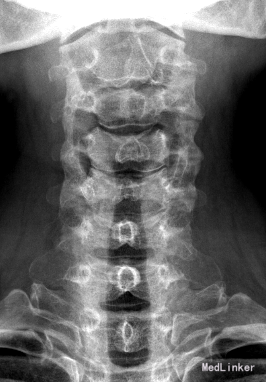

主诉:四肢乏力、蹲下困难2年,加重1月。 病史:患者于2年前无明显诱因出现四肢乏力及蹲下困难,双手支撑地面才能下蹲,无行走困难,无腰部酸痛,无双下肢疼痛、麻木感,大小二便未见异常。患者及家属未予以重视,未行任何诊治。1月前,患者诉四肢乏力及蹲下困难加重,无四肢疼痛、麻木感,大小二便未见异常。遂至外院行MR检查提示:颈6/7水平椎管内蛛网膜囊肿,并相应脊髓圆锥、马尾神经受压移位、聚集。遂收至我科行进一步诊治。患者一般情况较差。

查体:脊柱生理弯曲存在,无明显侧后凸畸形。颈6/7棘突有轻压痛。右侧膝反射未引出(-),左侧膝反射(+),右侧踝反射(+),左侧踝反射(++),双侧踝阵挛、Babinski征(-)。 辅查:肿瘤、生化等均未见明显异常,影像学主要如下:

诊断:颈椎椎管内肿物待查? 治疗:入院后完善相关检查,暂予对症治疗,经治疗组讨论决定,拟行“后路蛛网膜囊肿切除+栓系松解+钉棒内固定术”。